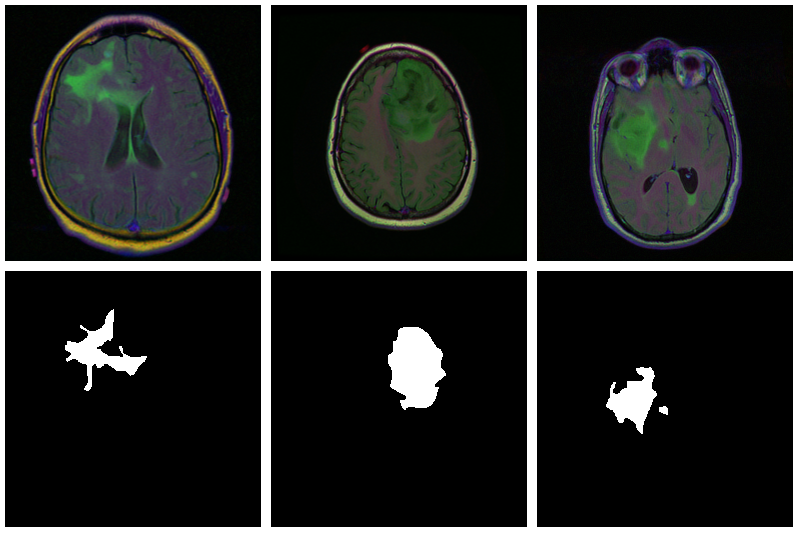

With U-Net, domain applicability is as broad as the architecture is flexible. Here, we want to detect abnormalities in brain scans. The dataset, used in Buda et al. (2019), contains MRI images together with manually created FLAIR abnormality segmentation masks. It is available on Kaggle .

As is often the case in medical imaging, there is notable class imbalance in the data. For every patient, sections have been taken at multiple positions. (Number of sections per patient varies.) Most sections do not exhibit any lesions; the corresponding masks are colored black everywhere.

Here are three examples where the masks do indicate abnormalities:

Let’s see if we can build a U-Net that generates such masks for us.